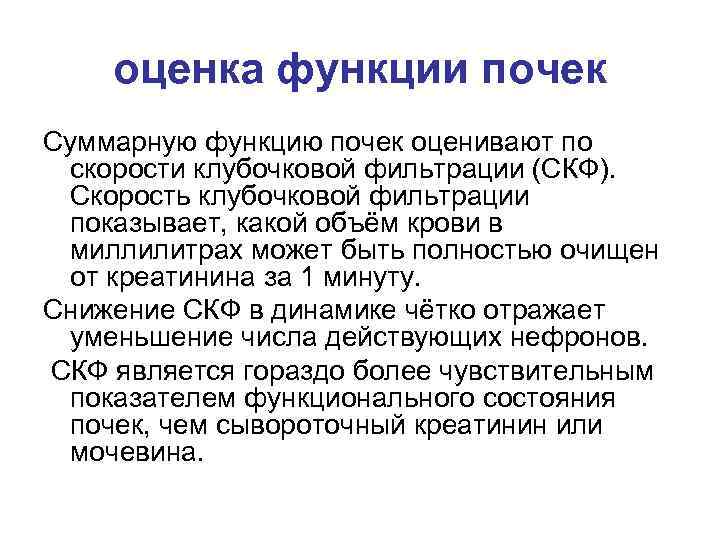

оценка функции почек Суммарную функцию почек оценивают по скорости клубочковой фильтрации (СКФ). Скорость клубочковой фильтрации показывает, какой объём крови в миллилитрах может быть полностью очищен от креатинина за 1 минуту. Снижение СКФ в динамике чётко отражает уменьшение числа действующих нефронов. СКФ является гораздо более чувствительным показателем функционального состояния почек, чем сывороточный креатинин или мочевина.

оценка функции почек Суммарную функцию почек оценивают по скорости клубочковой фильтрации (СКФ). Скорость клубочковой фильтрации показывает, какой объём крови в миллилитрах может быть полностью очищен от креатинина за 1 минуту. Снижение СКФ в динамике чётко отражает уменьшение числа действующих нефронов. СКФ является гораздо более чувствительным показателем функционального состояния почек, чем сывороточный креатинин или мочевина.